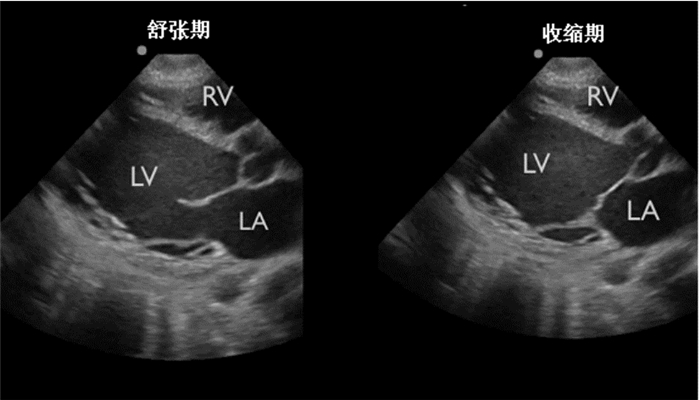

| 图 4 左心室收缩功能严重减低 |

收缩末期左室前后壁几乎贴近,称为“亲吻征”,高度提示左室充盈欠佳、容量不足,见于低血容量性休克(图 5)。

| 图 5 箭头示收缩末期左室前后壁几乎贴近,称为“亲吻征” |